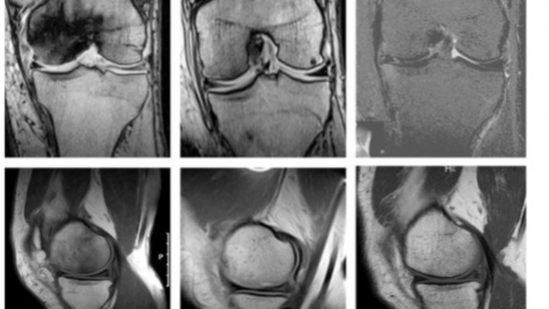

Methods: This retrospective study evaluates 37 ONK patients (29 male, 8 female; mean age ± 1 standard deviation: 54 ± 14); 83.7% of patients presented with Aglietti stage I-II; 16.3% presented with Aglietti stage III. Patients were treated with HBOT once a day, 5 days a week, at 2.5 ATA with 100% inspired oxygen by mask for an average of 67.9 ± 15 sessions. Magnetic resonance imaging was performed before HBOT, within 1 year after completion of HBOT, and in 14 patients, 7 years after treatment. Oxford Knee Scores (OKSs) were recorded before HBOT and at the end of each HBOT treatment cycle.

Results: After the 30 sessions of HBOT, 86% of patients experienced improvement in their OKS, 11% worsened, and 3% did not change. All patients improved in OKS after 50 sessions. Magnetic resonance imaging evaluation 1 year after HBOT completion showed that edema at the femoral condyle had resolved in all but 1 patient

Conclusions: HBOT is beneficial for treating ONK. Patients experienced improvements in pain and mobility as demonstrated by improvement in OKS. Radiographic improvements were also seen upon post-treatment follow-up. Aglietti staging for the entire sample saw an aggregate decrease (P < .01) from 1.7 ± 0.7 to 0.3 ± 0.6